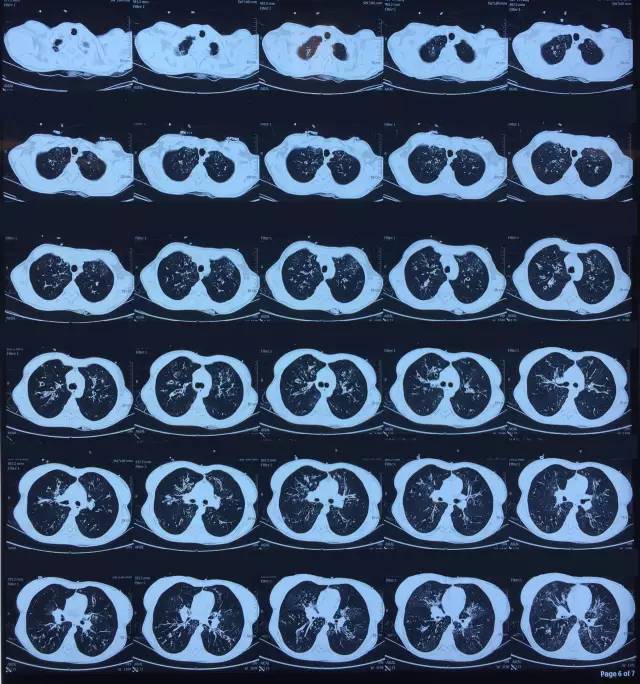

肺CT見(jiàn)下圖

該患者肺部影像學(xué)表現(xiàn)為明顯的支氣管擴(kuò)張,同時(shí)伴有彌漫的滲出斑片影���,考慮合并感染���,細(xì)菌學(xué)培養(yǎng)提示為綠膿桿菌,結(jié)合藥敏結(jié)果給予頭孢他啶+阿米卡星抗感染���,患者存在II型呼吸衰竭予氣管插管機(jī)械通氣支持���,加強(qiáng)體位引流排痰,治療18天���,患者情況好轉(zhuǎn)出院���。